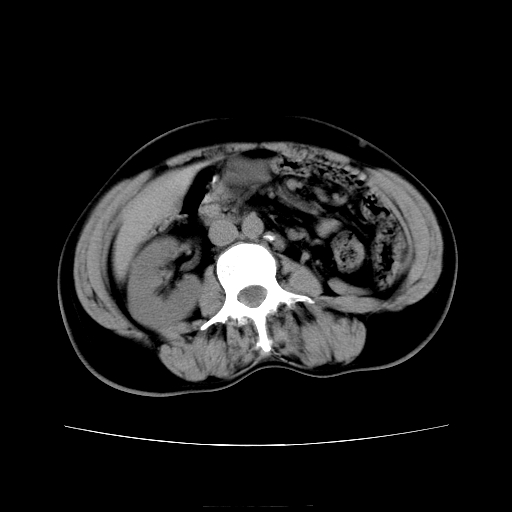

女45y多次(7次)碎石,结果不理想!曾碎石后尿出小碎石,仍腰痛,要求ct,其它不详.本人更倾向于钙化斑!无肾实质破坏,积水等提示集合系统无梗阻.另外腹腔多处钙化.是否结核后改变!谢谢赐教!

考虑双侧肾结石,碎石一般只用于输尿管,膀胱及尿道结石,肾结石特别是无梗阻的肾结石不主张采用碎石的,有可能会搞得收不了场,再者也效果不好,无甚必要,大可以手术

1)双肾结石。2)脾脏钙化灶。3)腹膜后多发淋巴结钙化。

尿路结石与腹部淋巴结钙化共存,建议v尿路造影检查,免得钙化灶冤枉为结石受罚。

考虑双肾结石,肾脏实质无破坏表现,没有结核病史,不考虑肾结核,